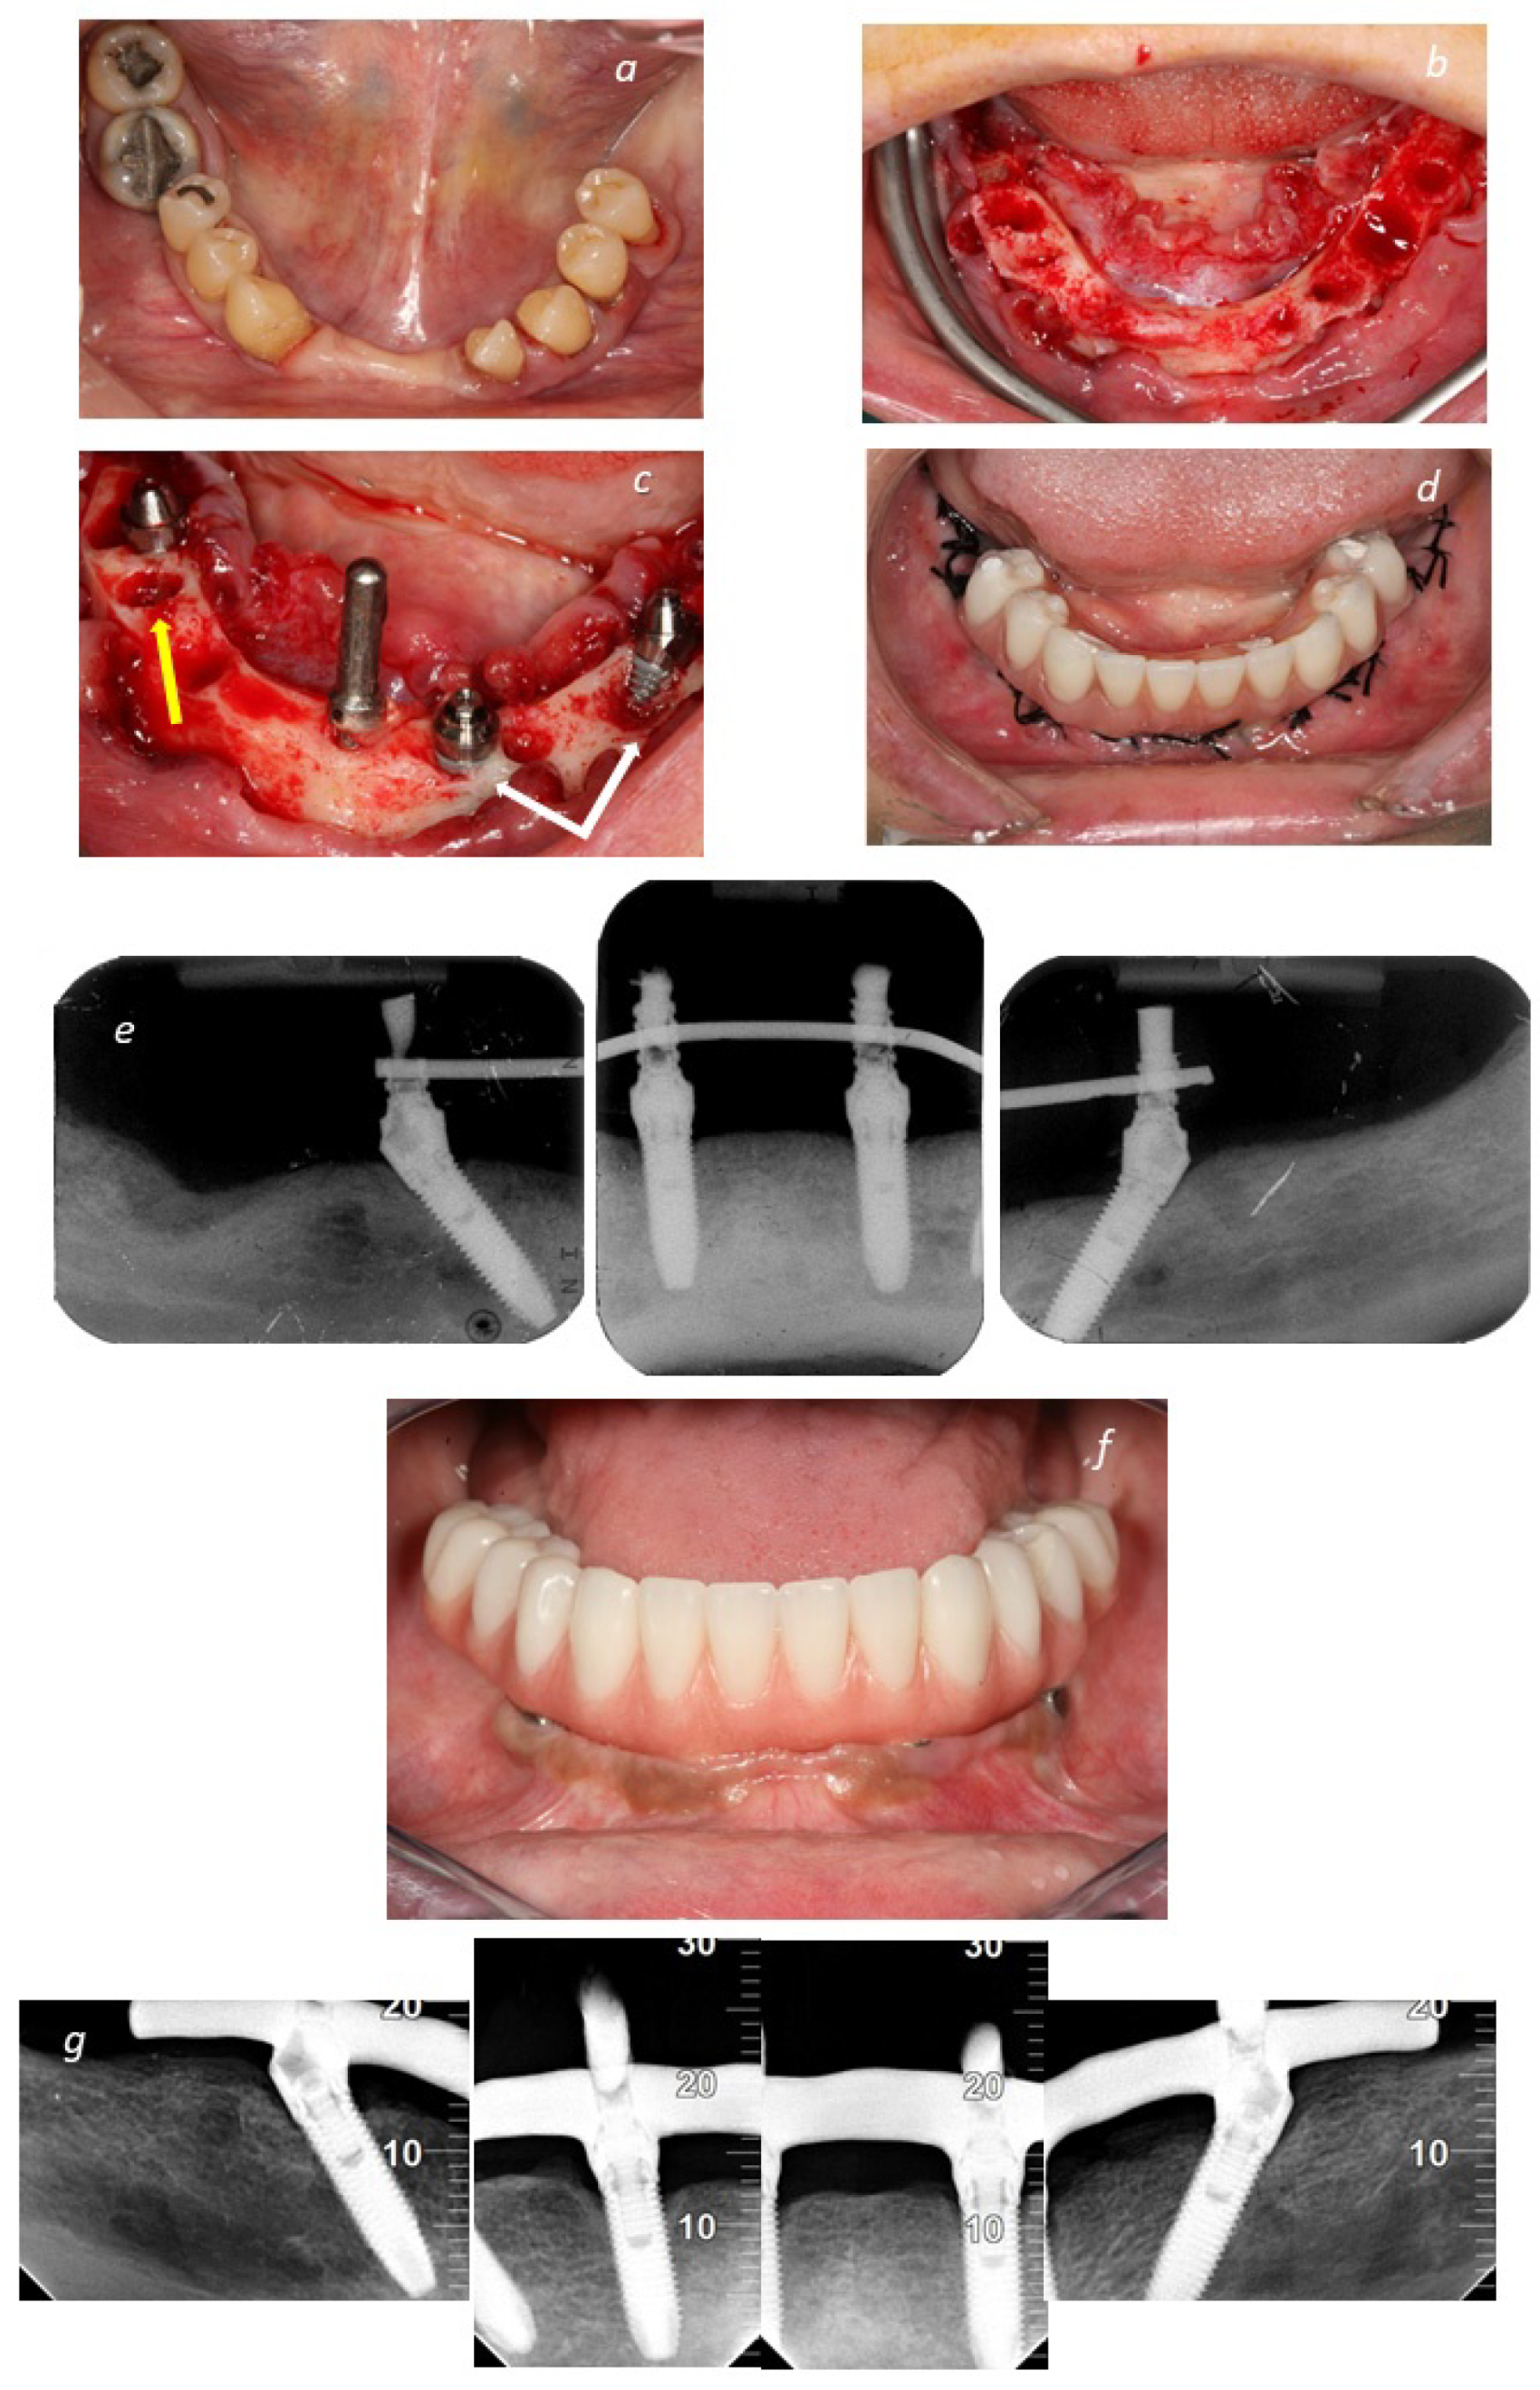

2. Materials and Methods